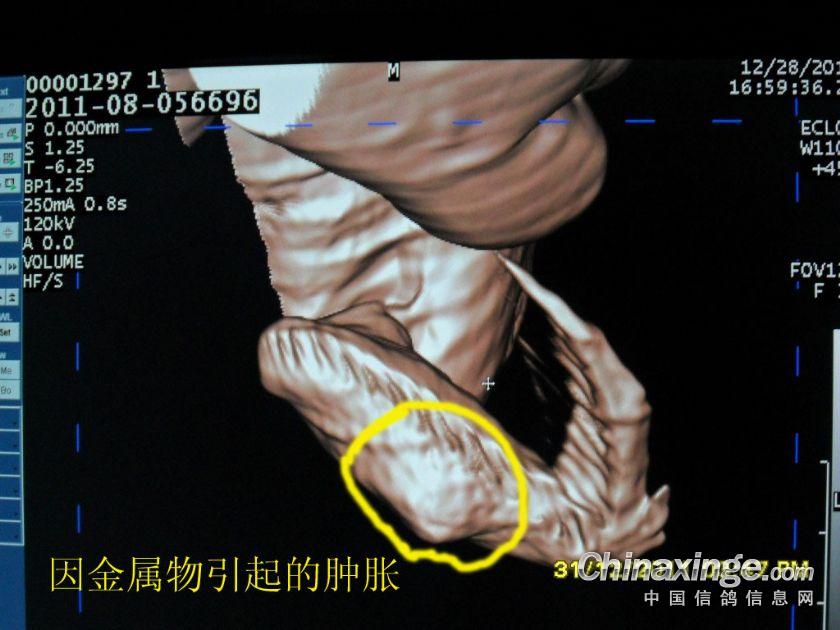

作品说明: 2011年秦皇岛BOB公棚四关宾利汽车大奖赛 2011-08-056696 雨点 雌 第一关 08-056696 116名 第二关 08-056696 59名 双关综合冠军 第三关 08-056696 37名 三关综合冠军(领先亚军332名,3天共归巢292羽) 第四关 08-056696 未归?开笼后只飞行了几公里被迫落下!被人拾到后发现“没有盖暗记的翅膀”内侧已经肿胀并且有一个疙瘩!!!

钢针插在翅膀内,翅膀肿胀,开笼后被迫落下!!!

肿胀的翅膀

在翅膀内的金属已经发炎